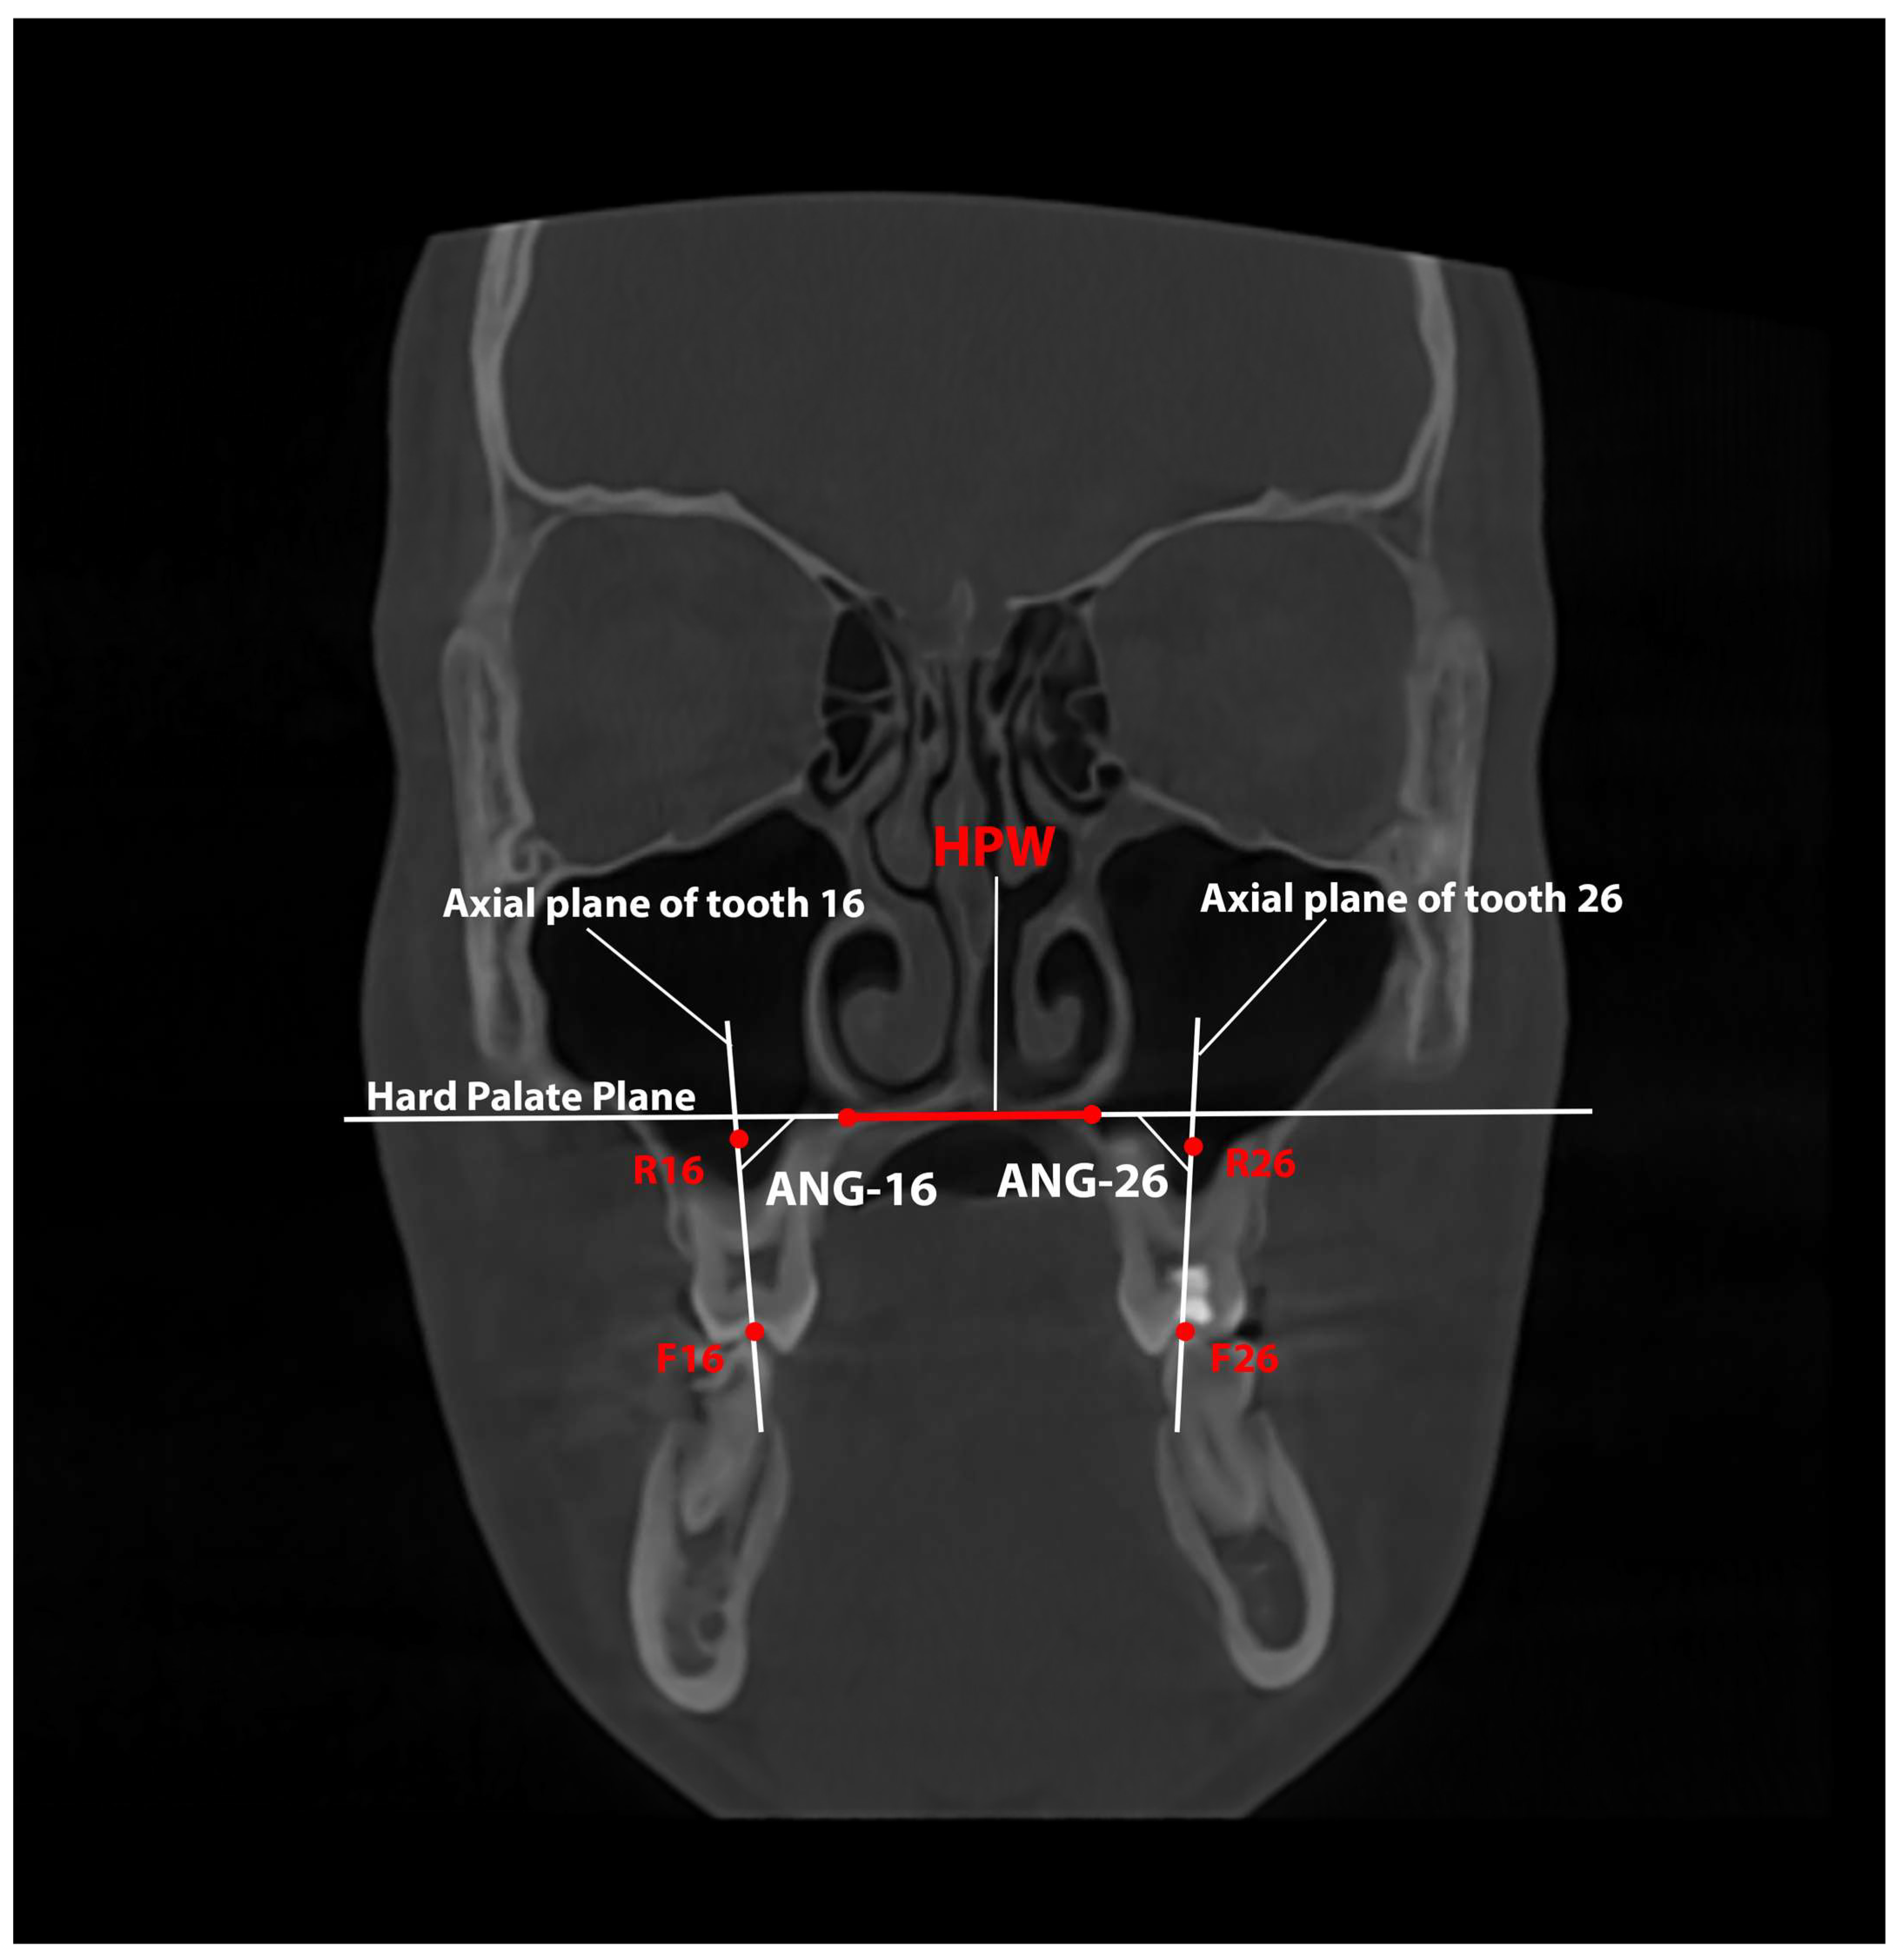

Measurements of the inclination of the right (ANG-16) and left (ANG-26) upper first molars relative to the HPW were also made. The measurements were performed before and after RME and were measured in degrees (Table 2 and Figure 4).

Figure 4.

Assessment of the inclination of the upper first molars relative to the plane of the hard palate measured on a CBCT coronal slice. The Hard Palate Width (HPW) is indicated with the red line and the corresponding plane is indicated in white. The red dots indicate the points (R16, R26, F16, and F26) that define the axial plane of the upper first molars (represented by the two vertical white lines).

As demonstrated in Table 5, the mean change in the inclination of the upper molars was not statistically significant (for tooth 16, the mean change was 0.600; for tooth 26, the mean change was 2.190). Furthermore, the standard deviation for tooth 16 was 6.420, and that for tooth 26 was 4.510. The minimum and maximum values for the parameter in question were deemed to be significant. However, these parameters were measured in individual patients. The wide angulation range obtained is related to the occlusal blockages from the unilateral posterior crossbites. The occlusal blockage acts as an additional anchorage for one of the upper molars, while the contralateral upper molar receives a higher force level, which results in its increased vestibular inclination, thus resulting in deviations from the mean values.

Judging by the mean values, there is relative stability with minimal molar inclination in the area of the first molars during maxillary expansion. This statement was supported by the mean values of MxOW and MxAW, where the roots of the first molars are actually located. Both variables, as shown in Table 4, have almost identical change (MxOW—3.64 mm and MxAW—3.68 mm). This suggests an almost bodily displacement of the upper first molars that is attributed to the digital planning and placement of the expansion screw at the level of the CR of the upper first molars, minimising the potential vertical deformation of the maxilla.